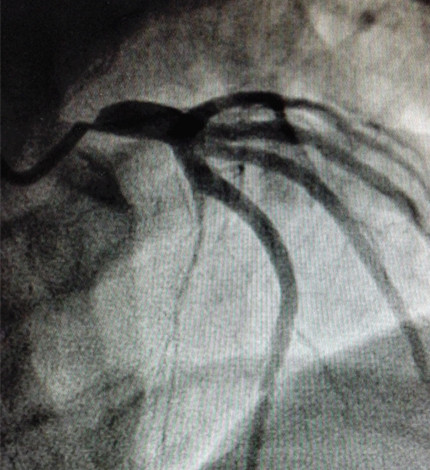

然而冠心病远非我们想象的那么简单,这位44岁的女性患者就是很好的例证。该患者主因“反复右侧胸痛”6月入院;既往身体健康;否认吸烟、高血压病及糖尿病等易患因素;该患者曾在多地药物治疗,效果不明显遂就诊于我院,入院后进行冠脉造影检查,结果提示左主干开口99%狭窄,左主干血管粗大。患者的造影结果超出所有人的预判,如果不采取介入或外科干预治疗,随时有发生猝死的风险。对于这种严重狭窄的左主干开口病变,国内外介入指南均列为高危复杂的病变,如果术中出现导管崁顿或支架贴壁不良,就有可能产生严重的恶性不良事件,许多医院只能选择外科冠脉搭桥手术;如果想通过微创介入处理该病变,往往需要血管内超声的帮助,还需要介入医师丰富的经验及过硬的胆识。对于该年轻患者,考虑到外科搭桥可能对患者造成的创伤大、术后恢复时间长等因素,张再伟博士还是建议对其进行介入治疗。在与患者家属沟通手术风险后,家属表示理解并愿意积极配合治疗,这给了张再伟博士极大的信心,遂于7月27日成功为患者实施介入手术,在左主干开口植入1枚支架,复查造影效果令人满意,患者症状明显好转,术后3天康复出院。

(手术前)